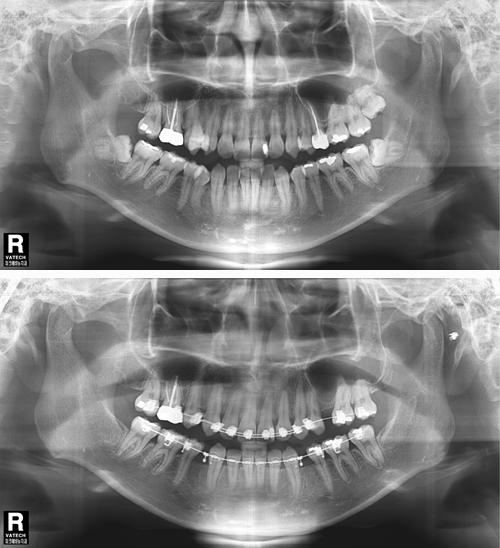

파크에비뉴치과 사랑니 발치 전 후 비교

위 두 환자는 교정치료를 위한 공간확보가 필요하여 사랑니 발치를 하게 되었다. 아래턱에 점선으로 표시 되어있는 하치조신경 다발이 사랑니 뿌리에 근접하여 지나가서 난이도가 높은 수술이었지만 3차원적 영상인 CT와 Panorama X-ray를 정밀 분석하여 발치 한 결과 신경 손상 없이 발치 할 수 있었다. 또한 두 환자 모두 “PRF(자가골성장인자)”를 이용해 사랑니 발치를 하여 부작용을 최소화 하였다.